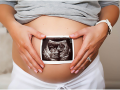

Ең

әдемі әйел – жүкті әйел. Өмірге сәби әкелетін жанның жүзінде тыныштық,

қорқыныш, жұмбақтық, еркелік қатар ұялап өзгеше түрге енеді. Жалпы

жүктілік (латынша: graviditas) әйел ағзасының ерекше құбылысы. Жүкті

әйелдер жүкті болмай тұрған кезде, жүктілік барысының дұрыс өтуіне

өздерін дайындап, дені сау ұрпақты дүниеге алып келуі керек. Ол үшін